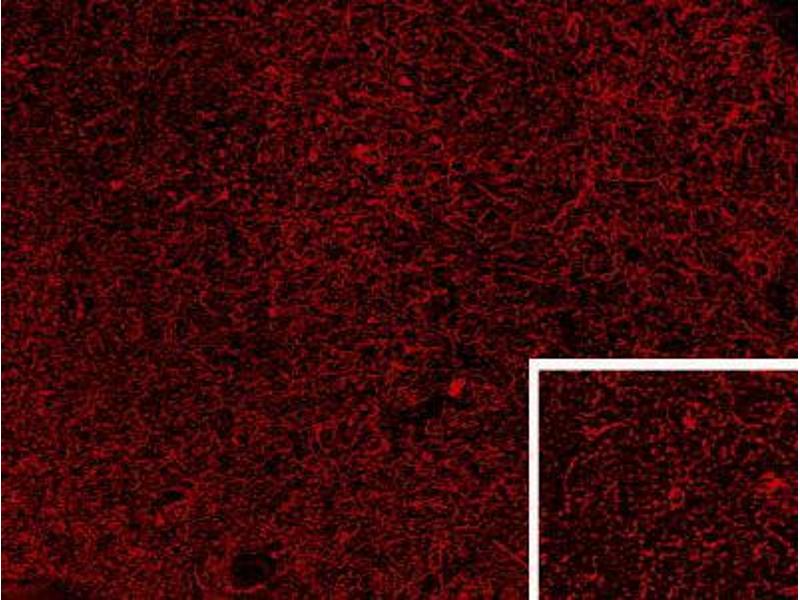

Immunohistochemistry: Frozen section of Human Hypothalamus shows staining of dense enkephalinergic axon plexus and scattered neuronal cell bodies (higher magnification inset) in the human infundibular nucleus. Recommended concentration: 0.3-1 μg/mL.